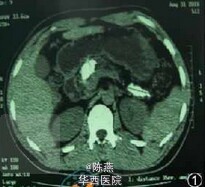

患者男,39岁,因反复上腹部疼痛4年,加重1个月入院。疼痛为阵发性,伴腰背部放射痛,曾在当地医院检查提示:胰管结石,经禁食、抗感染等治疗后疼痛缓解。患者疼痛反复发作,均经保守 治疗缓解。近1个月来疼痛剧烈,发作频繁,急诊收住我院治疗。 【既往病史】 既往曾有饮白酒史20年(100ml/d)。 【入院查体】 消痩貌,皮肤及巩膜无黄染,腹软,脐上方深压痛,无反跳痛,肝脾肋下未及,全腹叩诊呈鼓音,移动性浊音阴性,听诊肠鸣音正常。 【辅助检查】 血常规正常,血尿淀粉酶浓度正常。 腹部CT提示胰管明显扩张(图1 ),其内可见多发高密度影,最大约2.8cm×2.4cm。行手术治疗,术中见胰腺萎缩,质地变硬,胰管扩张直径2.0cm,胰头部及胰尾部可触及结石。切开胰腺被膜,顺胰管方向切开胰管,胰头及胰体部取出结石数枚,最大约3.0cm×2.4cm×2.0cm(图2,3),继续探查见胰尾部胰管狭窄,其内充满结石,行胰尾切除+胰管空肠Roux-en-Y吻合术(图3,4),手术顺利,术后患者恢复良好,腹痛消失,无脂肪泻、血糖浓度升高等并发症。术后胰腺组织病理切片呈慢性炎症表现(图5,6)。